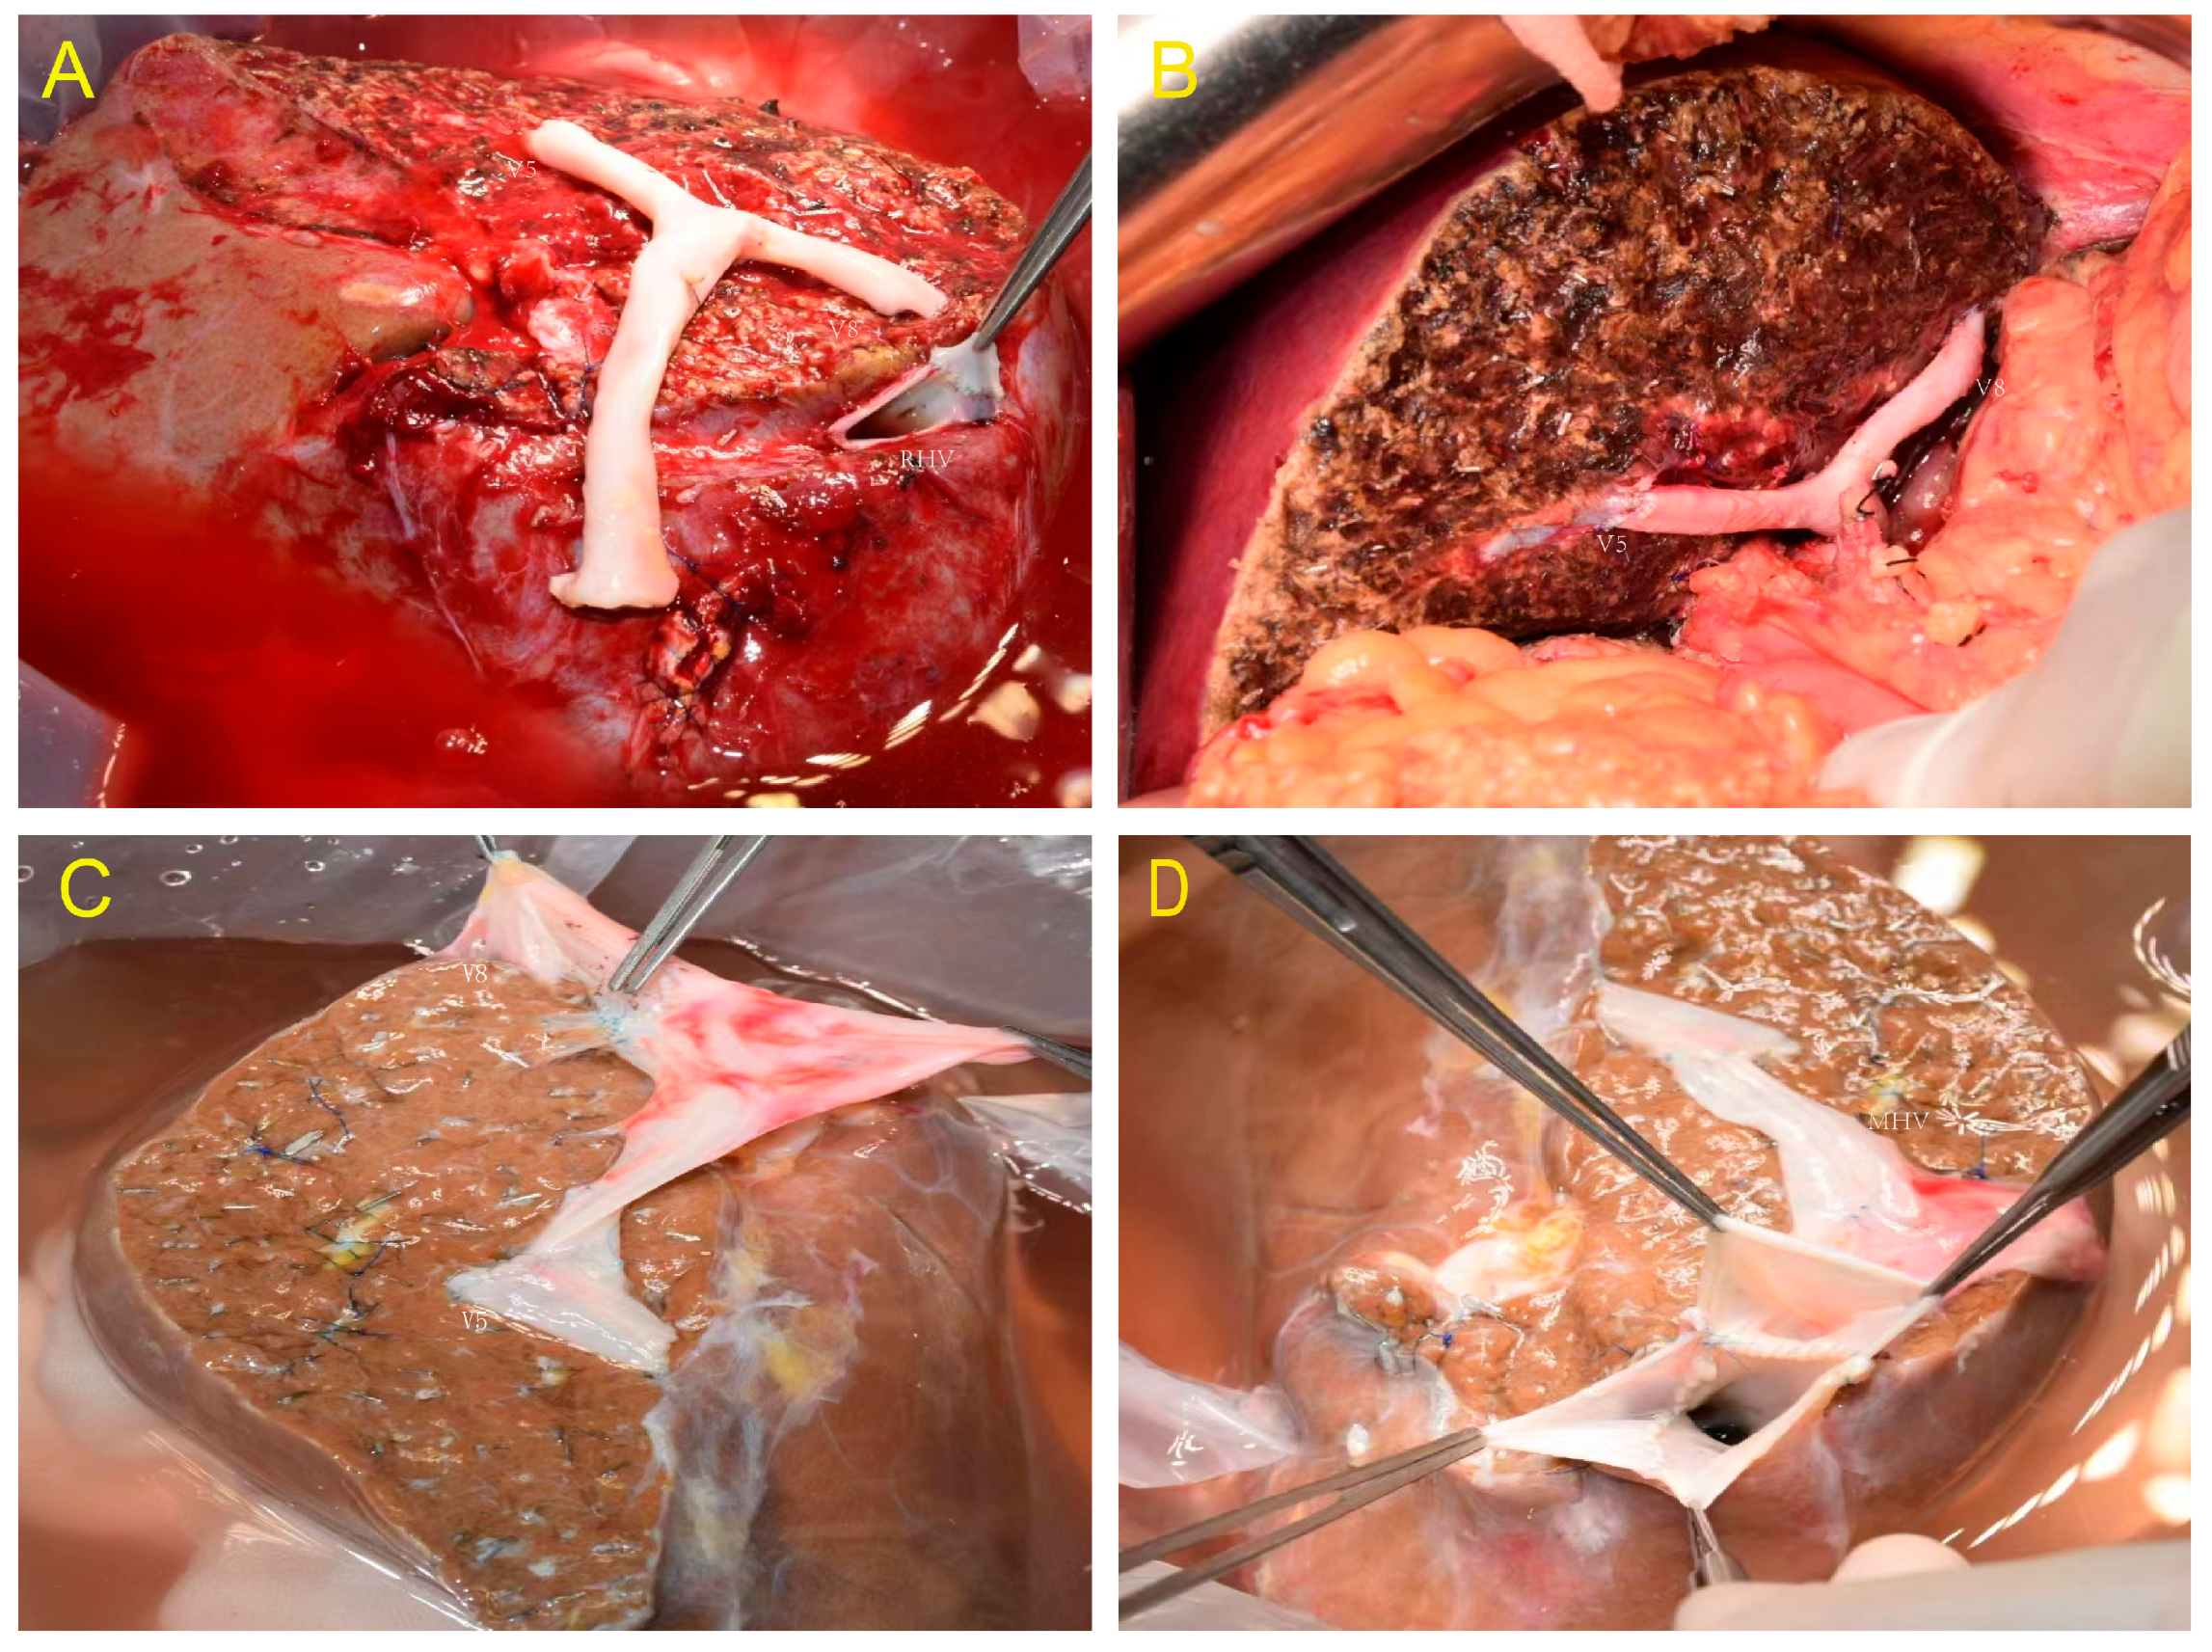

2.4. Donor Liver Harvest—Splitting Technique

2.5. Recipient Surgery